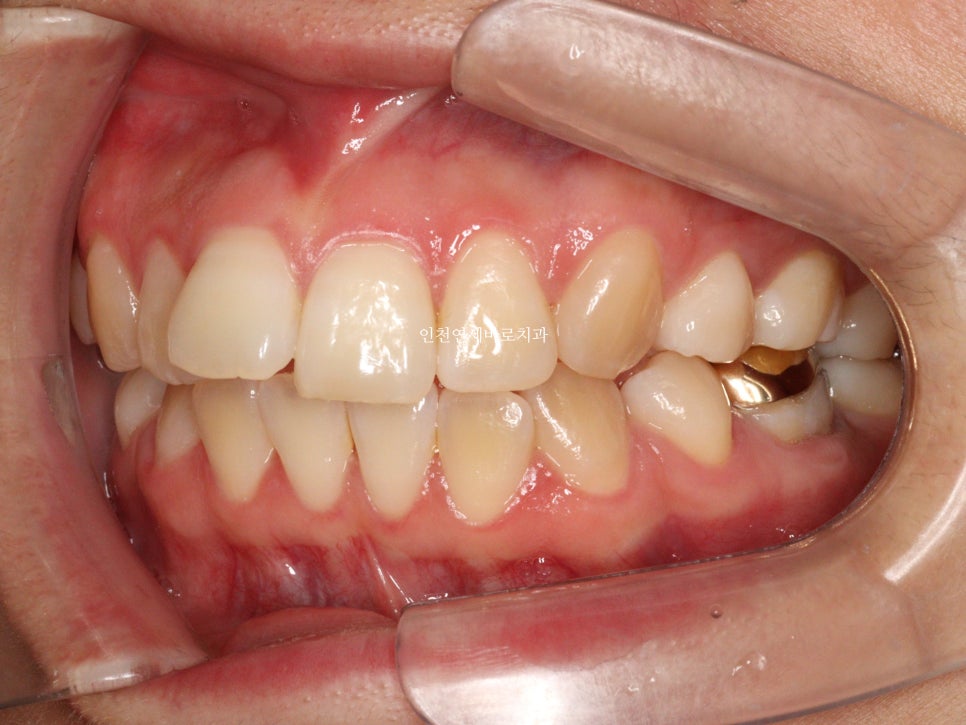

변화모습입니다.

약 3개월의 변화모습입니다.

그리고 치료가 마무리 된 후의 모습입니다.

부분교정으로 앞니만 철사를 붙여서도 비슷한 효과를 볼 수 있었을지 모릅니다.

하지만 치아의 삭제가 많은 양 동반되지 않았다면 앞니가 분명 뻗쳐나왔을것입니다.

하지만 인비절라인은 전체교정에 준하는

치아와 주변조직에 무리가 되지 않는 범위에서의 확장을 만들어낼 수 있어

앞니의 뻗침을 최소화 할 수 있는 장점이 있습니다.